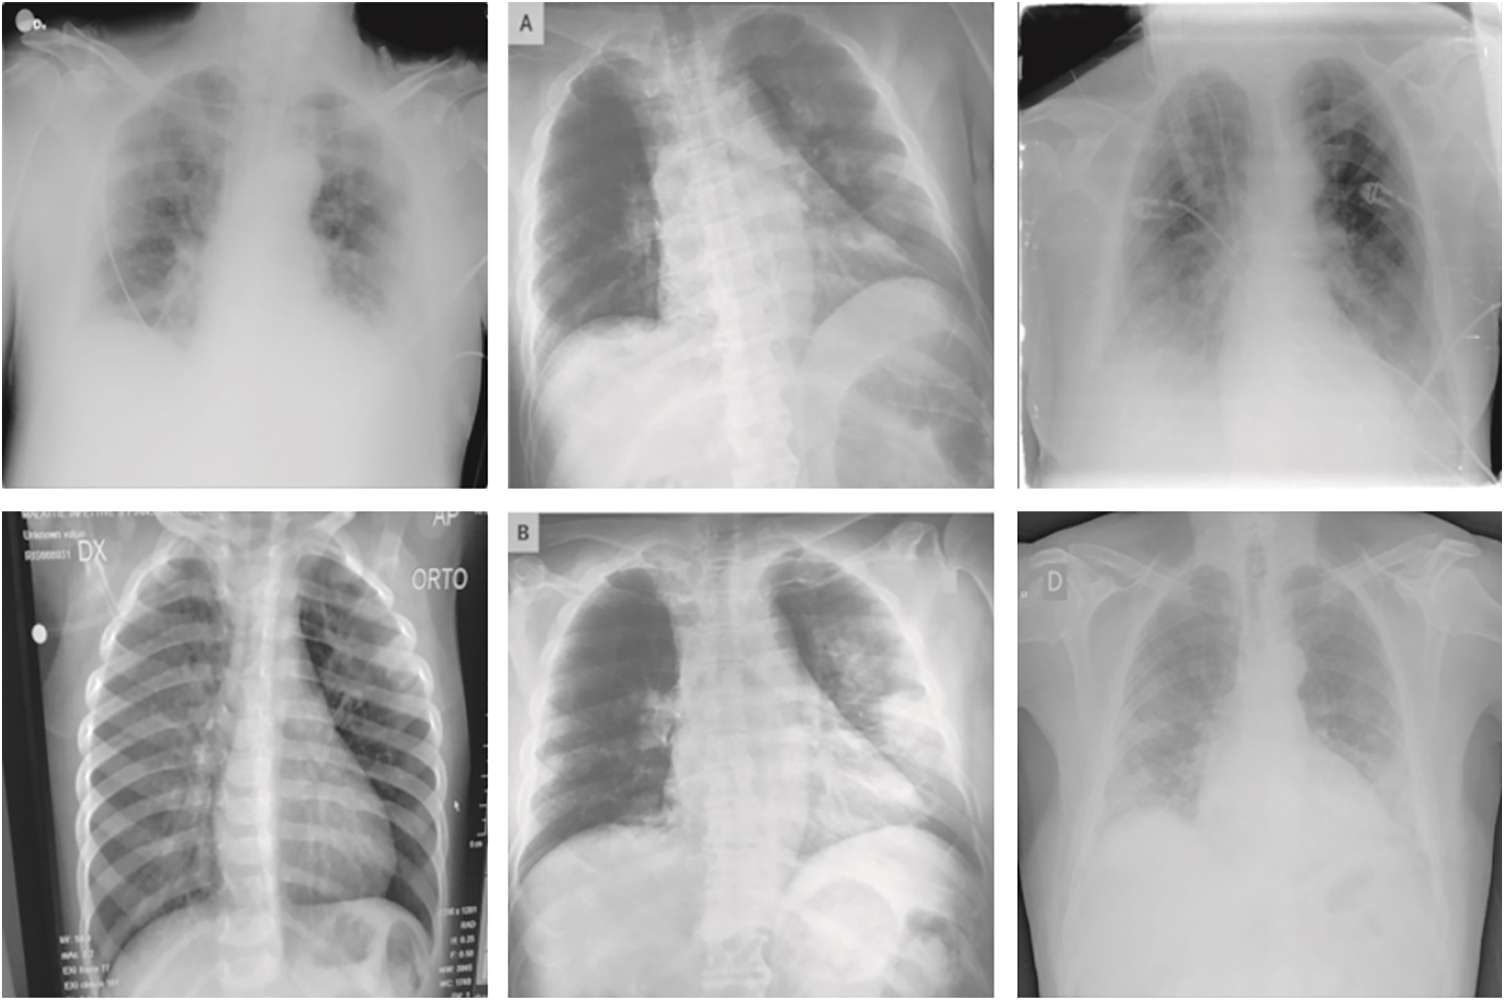

The performance validation of the QIDEXAI-CDC model is performed using the benchmark COVID-19 database from Kaggle repository (available at https://www.kaggle.com/tawsifurrahman/covid19-radiography-database). The dataset holds 3616 COVID images, 6012 Lung Opacity images, 10192 Normal images, and 1312 Viral Pneumonia images. In this work, 3500 images under each class are taken. A few sample images are illustrated in Fig. 4.

Figure 4: Sample images